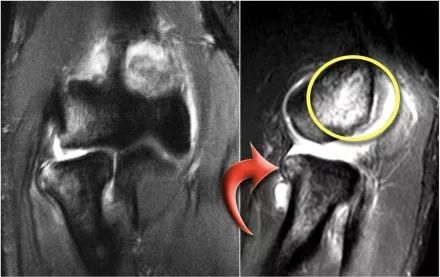

1.假的小凸起这是我们经常在冠状图像上看到。它看起来像是一个骨软骨病变,但是如果看一下矢状位图像,就会发现冠状图像穿过了髁骨的后关节部分,因此,当肘完全延伸,桡骨小头的一部分实际上是肱骨小头的后面。

在冠状视图上,我们将看到被软骨覆盖的桡骨头,并且与髁骨头的非软骨覆盖部分相对,其通常有些不规则。